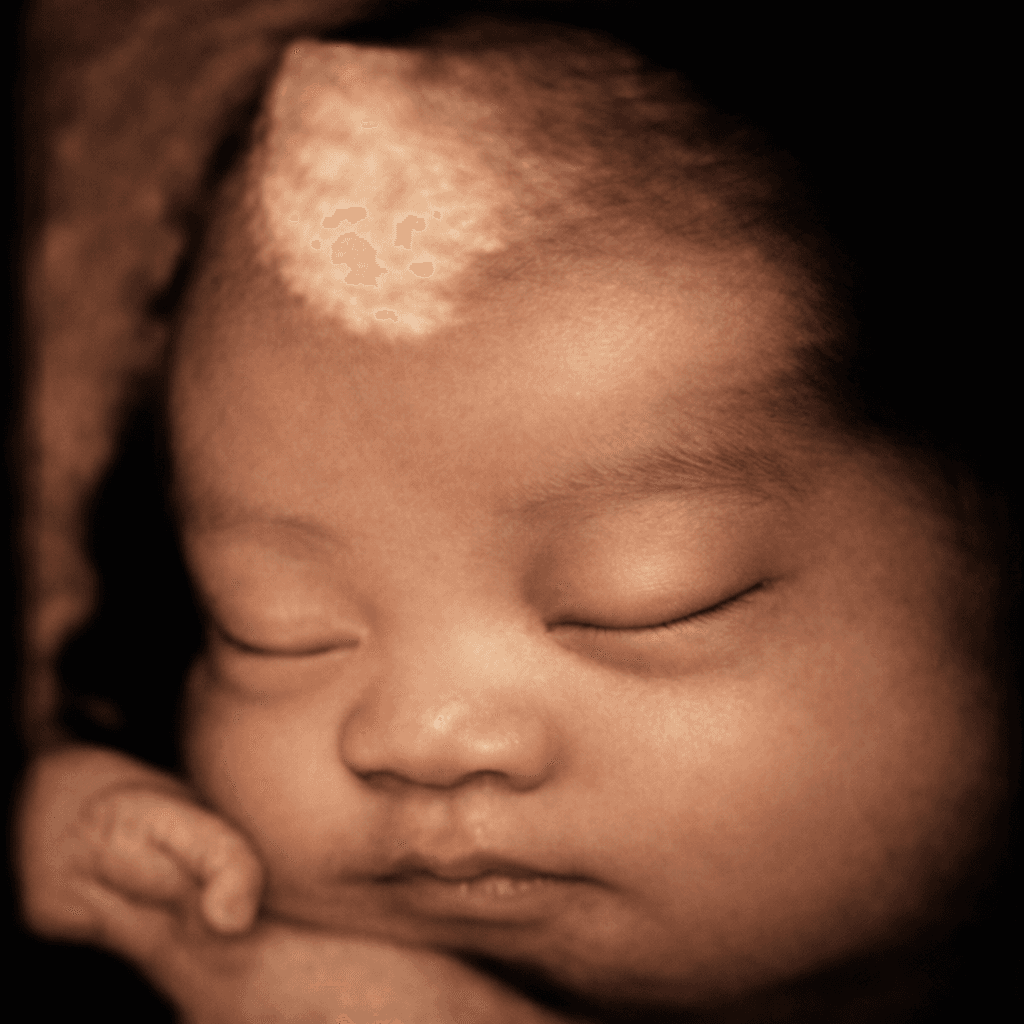

Vuốt để xem sự khác biệt giữa ảnh siêu âm gốc và hình ảnh AI làm nét